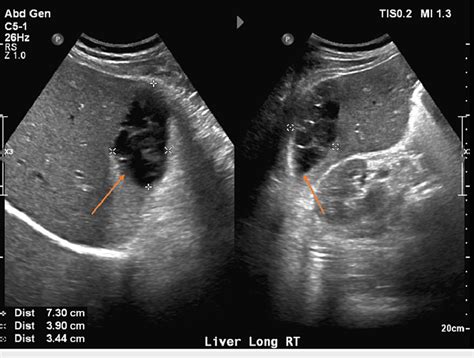

Echogenicity refers to the brightness or darkness of an area within an ultrasound image. It is crucial to distinguish various levels of echogenicity as it helps in identifying different structures. For instance, hyperechoic areas appear bright and represent tissues that reflect more ultrasound waves. On the other hand, hypoechoic areas are darker and indicate tissues that reflect fewer waves. Familiarize yourself with the typical echogenicity patterns of different organs to accurately interpret ultrasound images.

Shadowing is a phenomenon that occurs when sound waves encounter a highly reflective or attenuating structure in their path, resulting in a shadow-like appearance beyond that structure. This can make it challenging to assess structures that lie deep to the shadow. Understanding and recognizing shadowing is crucial to avoid misinterpretation and ensure accurate diagnoses. Recognizing the direction and extent of shadowing can provide valuable information about the underlying structures.

Shape recognition involves accurately identifying and assessing the shape of structures within an ultrasound image. This skill is particularly essential when examining organs such as the liver, kidneys, or uterus. By understanding the typical shape of these organs and comparing them to the observed images, you can determine if there are any abnormalities. Pay attention to any irregularities in contour, size, or symmetry, as they may indicate potential pathologies or conditions.

Tissue differentiation pertains to the ability to differentiate between various tissues or structures within an ultrasound image. This involves identifying different textures, borders, and echoes that characterize specific tissues. For example, differentiating between solid and cystic masses or distinguishing between a tumor and surrounding healthy tissue. Developing proficiency in tissue differentiation is crucial for accurate and precise ultrasound interpretation, enabling prompt and appropriate medical decisions.